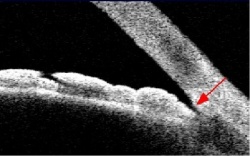

הדמייה לעצבי הראיה

בשנים האחרונות קיימות שיטות שונות להדמייה כמותית של עצבי הראיה. מכשירים אלה מאפשרים לספק מדדים שונים על עצב הראיה ומסביבו, כולל לגבי עובי העצב ושכבת הסיבים הנכנסת לתוכו. על-ידי השוואת המדדים הנמדדים לערכים באוכלוסיה בריאה ולערכים שנמדדו בעבר באותה העין ניתן להעזר בבדיקות אלה לאבחון גלאוקומה והערכת התקדמות המחלה.

בארץ המכשיר המוביל בצילום והדמיה של עצבי הראיה, הוא מכשיר ה- OCT (Optical Coherence Tomography).